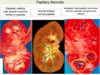

What is the histologic findings of acute kindey injury associated w/ ethylene glycol (aka anti-freeze)?

Often find what type of crystals in the tubular lumen?

- Marked ballooing and hydropic or vacuolar degeneration of PCT’s

- Calcium oxalate crystals